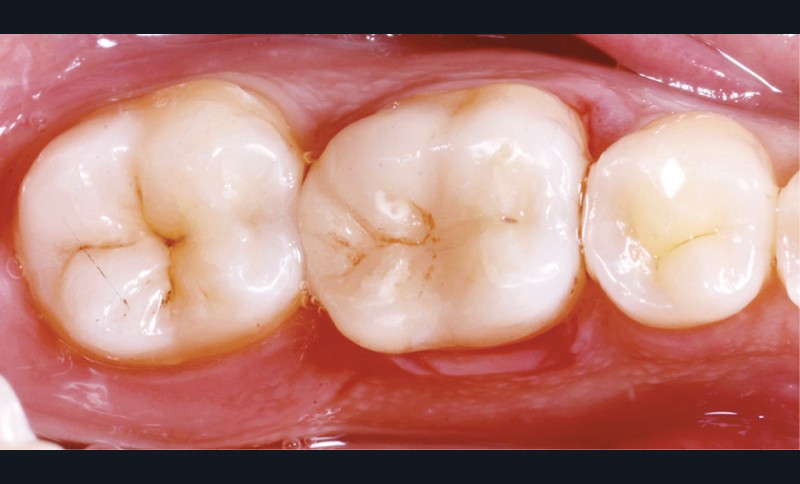

Lors de la préparation d’une cavité pour inlay/onlay, il est fréquent d’être confronté, en fin de nettoyage, à la présence d’une ou plusieurs parois résiduelles dont la résistance mécanique paraît douteuse du fait de leur localisation ou de leur épaisseur. Les parois épaisses (+ de 2 mm) peuvent généralement être conservées (cas clinique 1) et les parois fines (- de 1 mm) doivent généralement être recouvertes. Un inlay (en composite ou en céramique) est alors réalisé. Il doit avoir lui même, au final, une épaisseur globale minimale de 2 mm pour assurer sa résistance mécanique intrinsèque à la mastication. Si un recouvrement cuspidien est indiqué, la réduction occlusale doit donc se faire sur 2 mm de hauteur au minimum [1, 2].

La localisation (type de dent)

Le pronostic clinique semble plus favorable pour les prémolaires que pour les molaires [3-5], car une plus grande résistance est généralement nécessaire pour les parois des molaires. Mais si 75 % des fractures à la mandibule affectent les molaires, et plus particulièrement la première molaire, au maxillaire, les fractures se répartissent équitablement entre le secteur molaire et le secteur prémolaire [6]. L’épaisseur de l’émail, la largeur de la cuspide comme les…